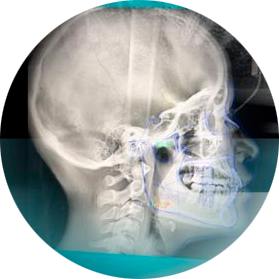

Estudios Radiológicos Digitales

• RX. Lateral de Cráneo

PANORÁMICA Y LATERAL

PANORÁMICA y LATERAL DE CRÁNEO